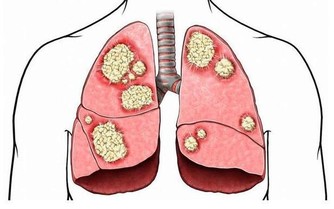

4.股骨頭壞死站「大」字

髖關節不好、股骨頭壞死的病人該怎麼鍛煉?趙之心教授說:

我教你一個鍛煉的竅門,我老家一個弟弟就是早期股骨頭壞死,鍛煉3個月就有好轉。

中老年人做的時候注意平衡性

沒事兒『大』字站——雙手水平伸直,左腿站好,右腿伸直向右側抬,然後左右腿交換,是不是像一個『大』字?

有的老年人一打噴嚏就髖骨骨折了,也能靠這樣來保健。